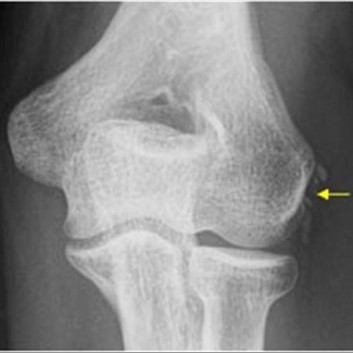

테니스 엘보는 팔꿈치 외측상과의 염증을 의미하며 골퍼엘보는 내측상과의 염증을 의미 합니다. 각각 테니스와 골프를 하다가 잘 발생한다고 하여 붙은 진단명 입니다.

팔꿈치 내측과 외측의 통증 모두 과사용에 인한 인대와 관절의 손상으로 인해서 발생 합니다. 꼭 운동이 아니더라도 일상 생활 속에서도 발생 가능 합니다. 손목과 팔꿈치를 계속해서 움직이게 되는 사무직 환경에서도 발생하며 신체 사용량이 많은 노동 환경에서도 발생 합니다. 만성적인 손상은 조직에 퇴행성 변화를 유발하게 되며 석회의 침착 및 관절의 변형 등을 관찰 할 수 있습니다.